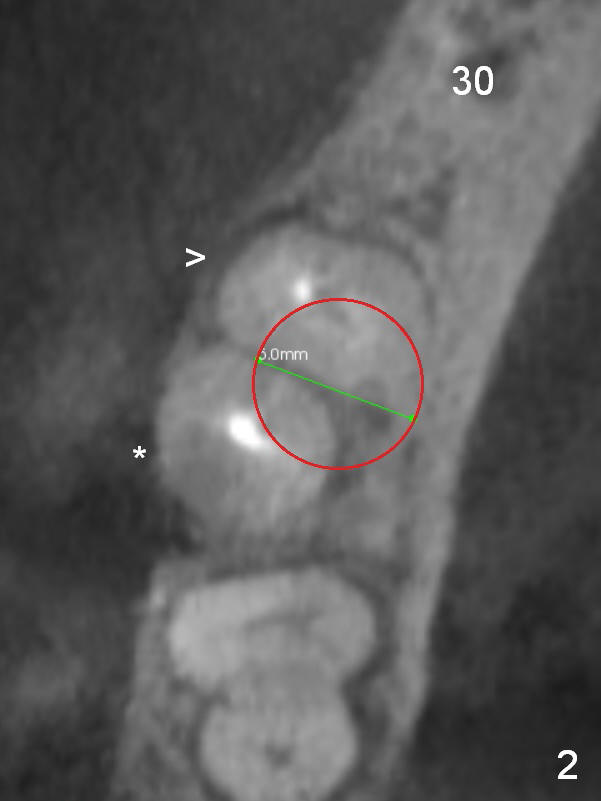

The narrow ridge at #30 will be split with wheel saw; osteotomy will be finished using bone expanders (Fig.4).